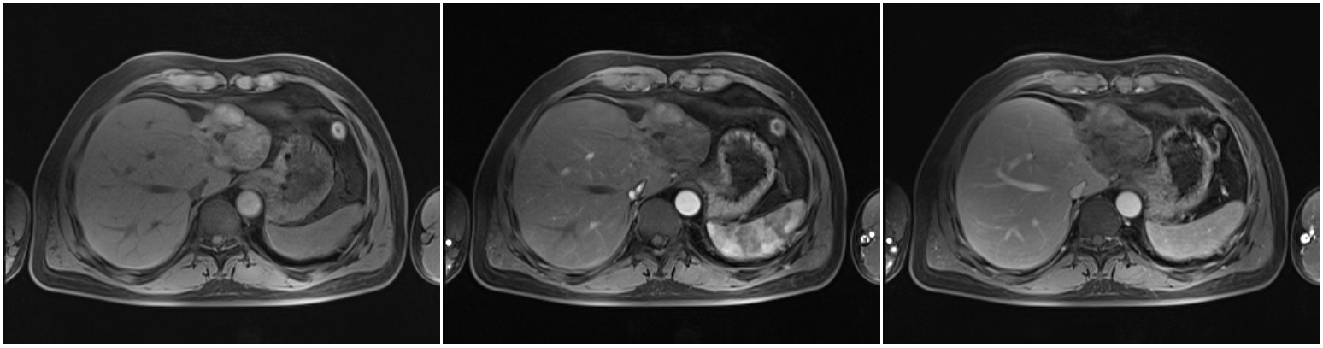

患者术后每6个月复查MRI,无瘤生存一年半。

2013-07-17复查上腹部MRI:肿瘤边缘出现复发病灶。

2013-07-22 对复发病灶再次行微波消融治疗

术后患者规律于我院复查:末次上腹部MRI(2017-08-26)复查未见明显复发病灶;2017年08月26日AFP:1.71ng/ml。后患者定期于当地医院复查AFP,均正常范围。